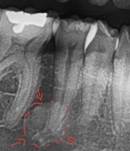

Osteítis condensante |

Asintomático lesión radiopaco-difusa con masa más o menos definido asociado al ápice del diente afectado se ve esclerótica no expandible.5 |

|